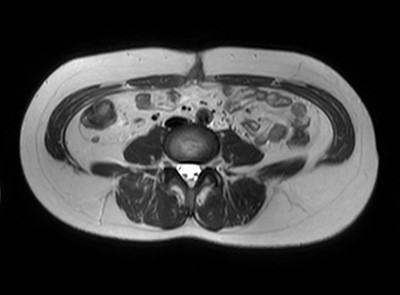

A 47-year-old woman was referred to us by her obstetrician. She developed a PHS after laparoscopic total hysterectomy with right oophorectomy performed 3 years previously. She reported pain with intermittent bulging on the superior aspect of the umbilical region. Clinical examination revealed a single hernia orifice at that location. Her height was 161.1 cm, with a weight of 60.1 kg, yielding a body mass index of 23.16 kg/m2. Her medical history included uterine fibroids and ovarian cysts. She had no history of smoking. Magnetic resonance imaging (MRI) revealed protrusion of adipose tissue at the upper side of the umbilical region, through a fascial defect measuring 9 × 13 mm; diastasis recti was also noted (Figs 1 and 2).

The patient did well after surgery. Follow-up MRI taken 10 days after surgery confirmed the absence of hernia and closure of the fascial defect (Figs 9 and 10).